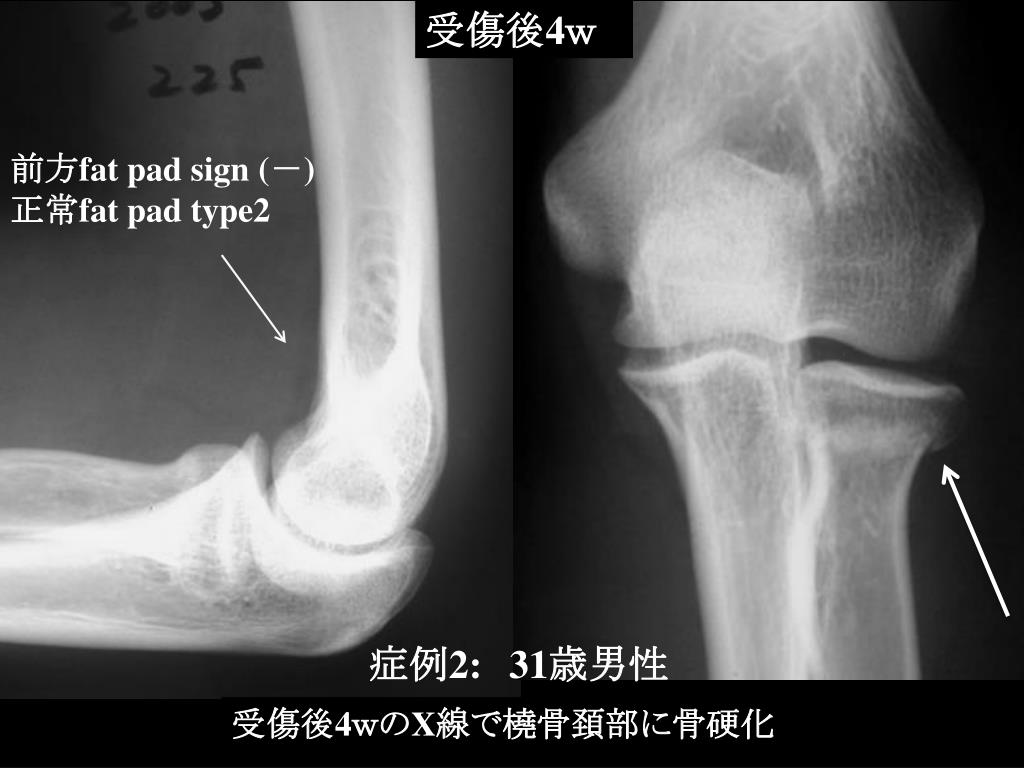

10. 受傷後4w 前方fat pad sign(-) 正常fat pad type2 症例2:31歳男性 受傷後4wのX線で橈骨頚部に骨硬化